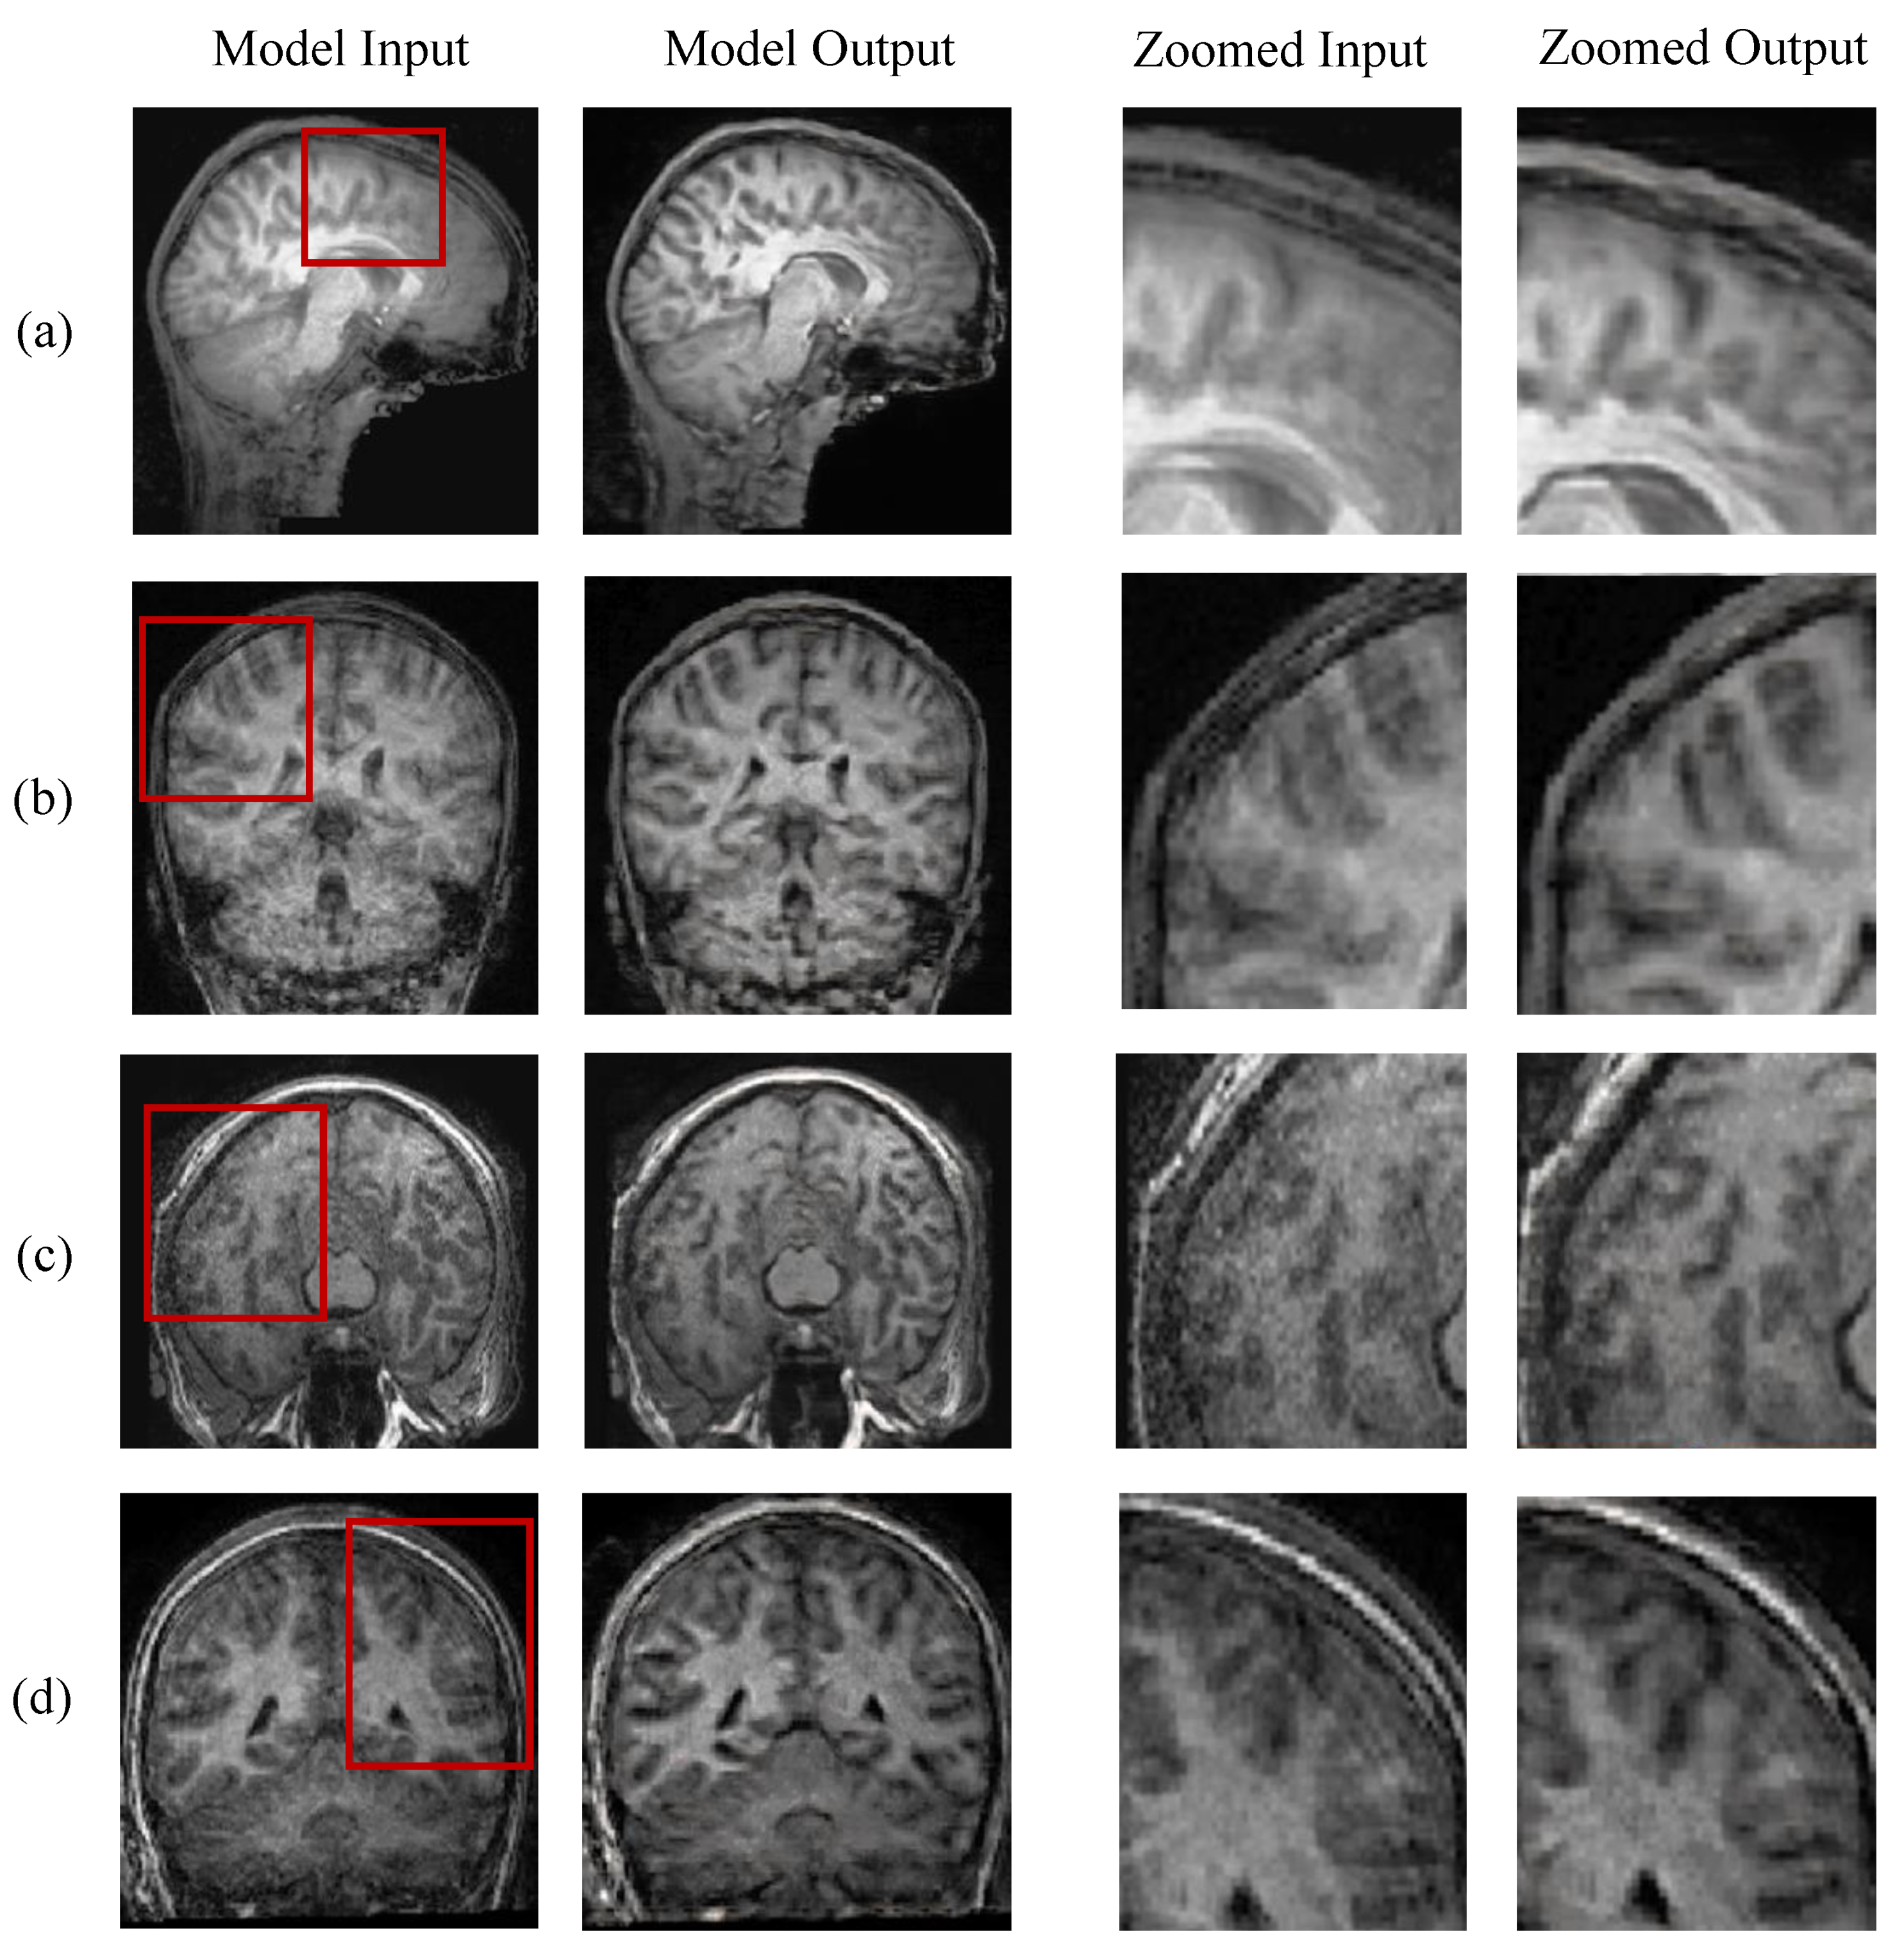

Evaluation on Synthetic Images

5.3. Evaluation on Real-World Scans